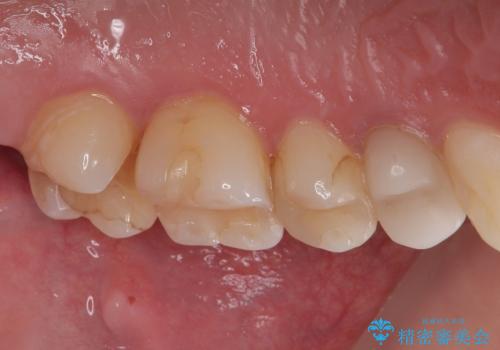

- プラスチックの詰め物が取れたとのことで来院された患者様です。神経の状態を検査し、正常な状態を確認してから残っている自分の歯の量を考慮しセラミックインレーにて修復しました。

セラミックインレーは、むし歯で削った部分に天然歯に近い白さと透明感をもつセラミック素材を詰める治療です。

金属を使わないため、見た目が自然で、金属アレルギーの心配もありません。

汚れや着色がつきにくく、精密に作製することで歯とのすき間が少なく、再発リスクを抑えられるのも大きなメリットです。

見た目の美しさと長期的な健康を重視したい方におすすめの治療です。